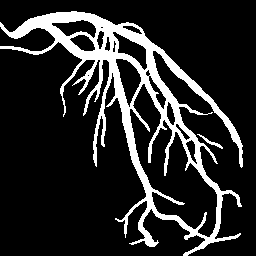

Blood vessel segmentation is crucial for many diagnostic and research applications. In recent years, CNN-based models have leaded to breakthroughs in the task of segmentation, however, such methods usually lose high-frequency information like object boundaries and subtle structures, which are vital to vessel segmentation. To tackle this issue, we propose Boundary Enhancement and Feature Denoising (BEFD) module to facilitate the network ability of extracting boundary information in semantic segmentation, which can be integrated into arbitrary encoder-decoder architecture in an end-to-end way. By introducing Sobel edge detector, the network is able to acquire additional edge prior, thus enhancing boundary in an unsupervised manner for medical image segmentation. In addition, we also utilize a denoising block to reduce the noise hidden in the low-level features. Experimental results on retinal vessel dataset and angiocarpy dataset demonstrate the superior performance of the new BEFD module.

翻译:近些年来,有线电视新闻网的模型导致分离任务突破,然而,这类方法通常会失去物体边界和对船只分割至关重要的微妙结构等高频信息;为解决这一问题,我们提议加强边界和地貌分解模块,以促进网络能力,在语义分解中提取边界信息,这种信息可以以端到端的方式纳入任意编码器-分解器结构。通过引入索贝尔边缘探测器,网络能够在之前获得更多边缘,从而以不受监督的方式加强医疗图像分解的边界。此外,我们还利用一个分解区块来减少低层特征中隐藏的噪音。关于再生容器数据集的实验结果和血管合成数据集显示了新的BEFD模块的优异性性表现。